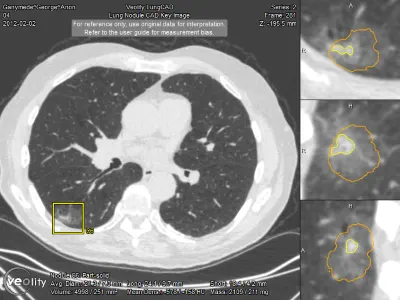

Veolity LungCAD bietet in der Lungenkrebsdiagnostik für Thorax CT-Aufnahmen eine vollständig integrierte KI-gestützte Detektion (CAD) solider Lungenrundherde.

Die Software ermöglicht eine zeiteffiziente und sichere radiologische Befundung von MSCT-Aufnahmen im klinischen Alltag. Veolity LungCAD verbessert die diagnostische Qualität in der Lungendiagnostik und macht komplexe Verlaufskontrollen einfach und effizient. Die besonders praktische automatische Segmentierung der Lungenrundherde mit Volumenmessung hilft Radiologen, reproduzierbare und vergleichbare Ergebnisse zu erzielen. Die Resultate werden einfach in die bestehende IT-Infrastruktur integriert. Radiologen profitieren von den automatischen CAD-Ergebnissen und behalten gleichzeitig die volle Kontrolle über ihren Diagnoseprozess.